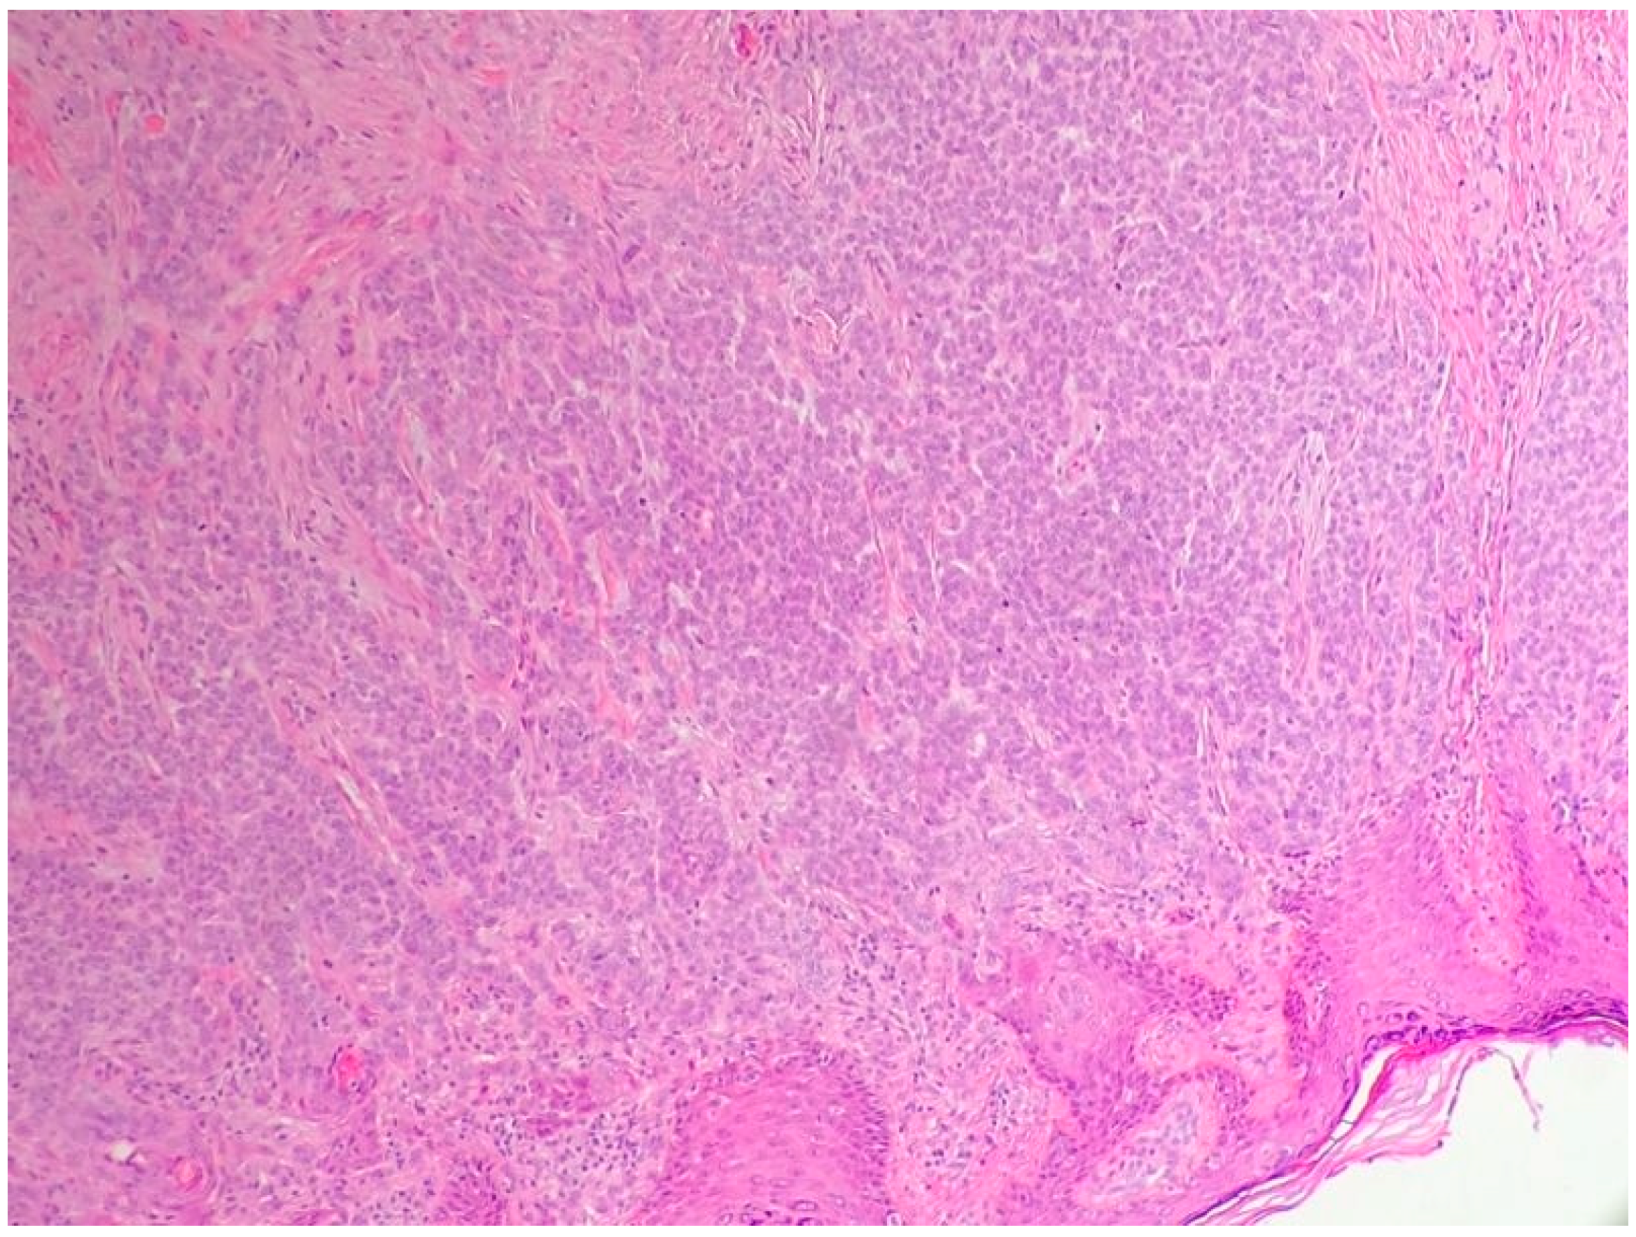

2.1. Basal Cell Carcinoma and Its Histological Variants

2.1.2. Main Histologic Variants